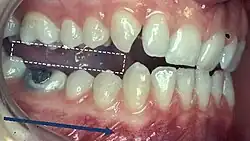

Canine Guidance

- Dynamic occlusion that occurs on the canines (on the working side) during lateral excursions of the mandible.

- These teeth are best suited to accept horizontal forces in eccentric movements due to their long roots and good crown/root ratio

- The influence of the contacting surfaces of the mandibular and maxillary incisors on mandibular movements[12] is characterised by the overbite and overjet of the maxillary incisors.